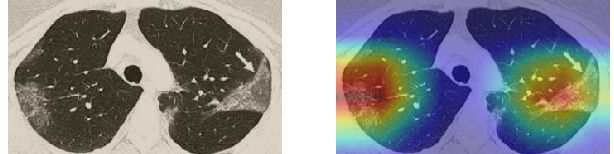

In order to make our models more transparent and provide detailed visual analysis, we present the Grad-CAM localization maps obtained by different models. We consider CT images with COVID-19 abnormalities from the test set of each dataset and highlight the important regions considered for the prediction. For the SARS-CoV-2 dataset we use the Inception V3 model. Figure 13 shows the original CT images and their localization maps. Our model is capable to detect regions that show abnormalities in the CT scans.

In a similar way, we consider classifying the test CT scans from the COVID-19 dataset by the DenseNet169 model and highlight the important regions considered for predictions. We present the original CT images and their localization maps in Figure 13. We can also see that our model is capable to detect the COVID-19 related regions as marked (small square in some images) by expert radiologists.